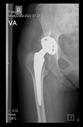

The radiological examination allowed us to verify the close bone-to-implant contact and the unchanged position of the implant during follow-up.

In all the cases operated with the above-described targeting procedure, the stems of the cups remained between the cortical bone surfaces without perforation of the linea terminalis, as shown by postoperative radiographs. There were no complicated surgical situations. In 16 cases, the wound healings were uneventful, and the hips were able to bear weight again after postoperative rehabilitation.